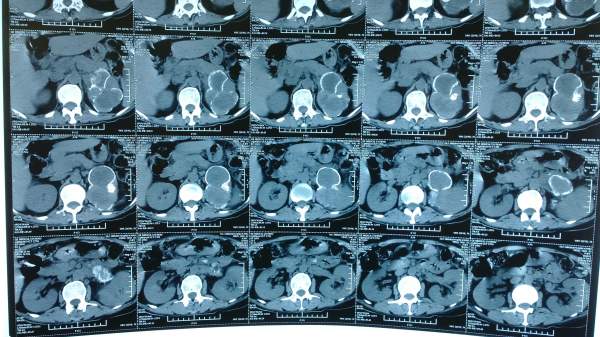

肾癌合并肾动脉血栓形成CT读片

近期在临床发现一个病例,病人因腰痛入院,查有肾动脉部分分支阻塞,肾脏占位,遂拍CT片,但是后来看不懂肾动脉的阻塞,不知在哪个部位,已经与肾脏占位的关系,现发上来,与大家分享一下,顺便求高手给予解答! IMG_20130904_112041.jpg IMG_20130904_112103.jpg |